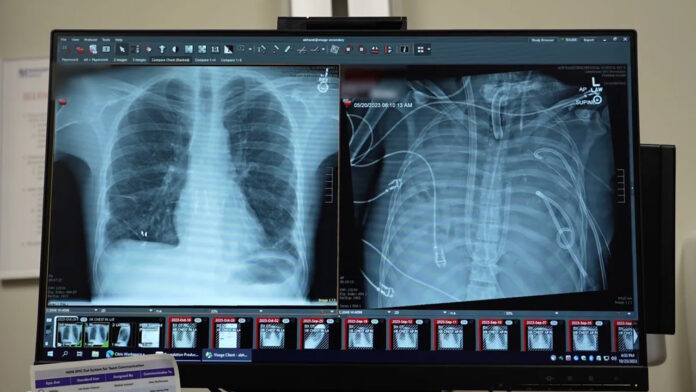

Şiddetli bir enfeksiyon nedeniyle akciğerleri tamamen çıkarılan bir hasta, yapay destekle nakil gününe kadar hayatta tutuldu. Uzmanlara göre bu yöntem birçok hastaya umut olabilir.